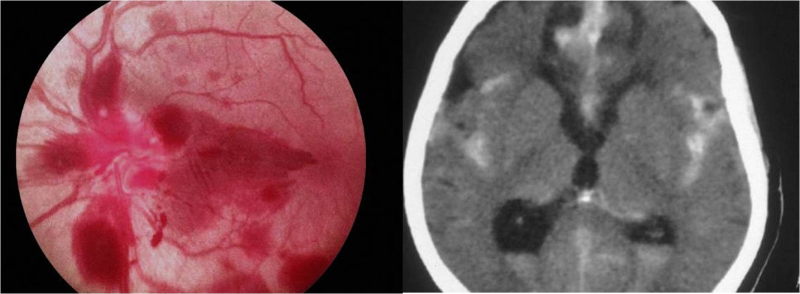

- Papiledema

El papiledema, por definición, es el edema de papila producido por el aumento de presión intracraneal (PIC). La RM craneal es la prueba de elección para su estudio causal, pero el carácter urgente de esta patología hace que habitualmente sea una TC craneal el primer paso en el protocolo diagnóstico. La TC tiene más utilidad en el caso de que se aprecien hemorragias en el fondo de ojo, pues permite identificar rápidamente un sangrado intracraneal agudo (Figura 2).

Figura 2. Borramiento papilar con múltiples hemorragias retinianas adyacentes (izquierda) y hemorrragia subaracnoidea en TC (derecha)

Si existe la sospecha de una trombosis venosa se completará el estudio con una angio-TC venosa, y en su defecto mediante RM. Cuando se descarta la presencia de una masa intracraneal es preciso realizar una punción lumbar para medir la PIC y analizar el líquido cefalorraquídeo (LCR) La RM craneal mantiene su valor, principalmente en casos atípicos de supuesta hipertensión intracraneal idiopática. La RM espinal está indicada en los casos de papiledema con presencia de células patológicas o aumento de proteínas en el LCR, cuando existen síntomas que orientan a patología medular o cuando las pruebas anteriormente mencionadas son normales (Figura 3).